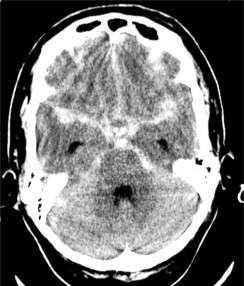

El manejo de la hemorragia subaracnoidea, ya sea traumática o espontánea, requiere una evaluación rápida y una intervención médica adecuada. El diagnóstico generalmente se realiza mediante tomografía computarizada o resonancia magnética, que permiten visualizar el sangrado y determinar su extensión. La identificación de la causa subyacente, como la presencia de aneurismas o malformaciones arteriovenosas, es crucial para establecer un plan de tratamiento.

La tomografía computarizada, preferiblemente acompañada de una angiografía por tomografía computarizada, debe realizarse de inmediato en pacientes con sospecha de hemorragia subaracnoidea. Este enfoque diagnóstico es crucial para confirmar la presencia de sangrado y para buscar pistas sobre su origen. La tomografía computarizada es preferida en comparación con la resonancia magnética debido a su rapidez y su mayor sensibilidad para detectar hemorragia en las primeras veinticuatro horas tras el evento. Sin embargo, es importante señalar que en algunos casos los hallazgos tomográficos pueden ser normales, lo que obliga a realizar un análisis del líquido cefalorraquídeo para detectar la presencia de glóbulos rojos o xantocromía antes de descartar la posibilidad de una hemorragia subaracnoidea.